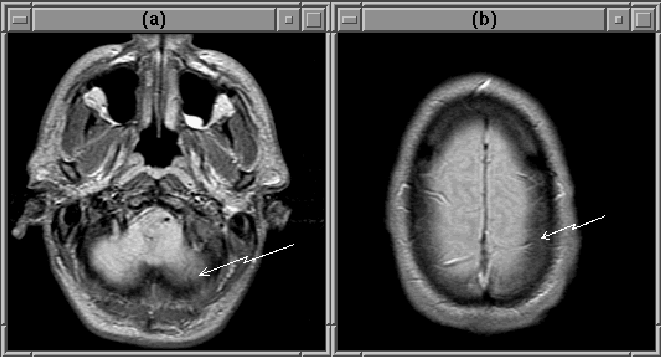

The partial volume effect is particularly noticeable in the extreme slices of MRI volumes. Figure 2.6 contains the first and last slice of a PD-weighted MRI data set. Brain tissue in the lower right of the first slice appears dim because tissues below the brain (with smaller FID response signals) contribute to the intensity of the slice. The boundary of the brain in the last slice is blurred because the voxels in that area represent both brain and cerebral spinal fluid (CSF). Obviously, the partial volume effect can hinder the detection of the intracranial boundary.

Figure 2.6: The partial volume effect results in dim brain tissue in the first MRI slice (a) and blurs the edge of the brain in the last slice (b).